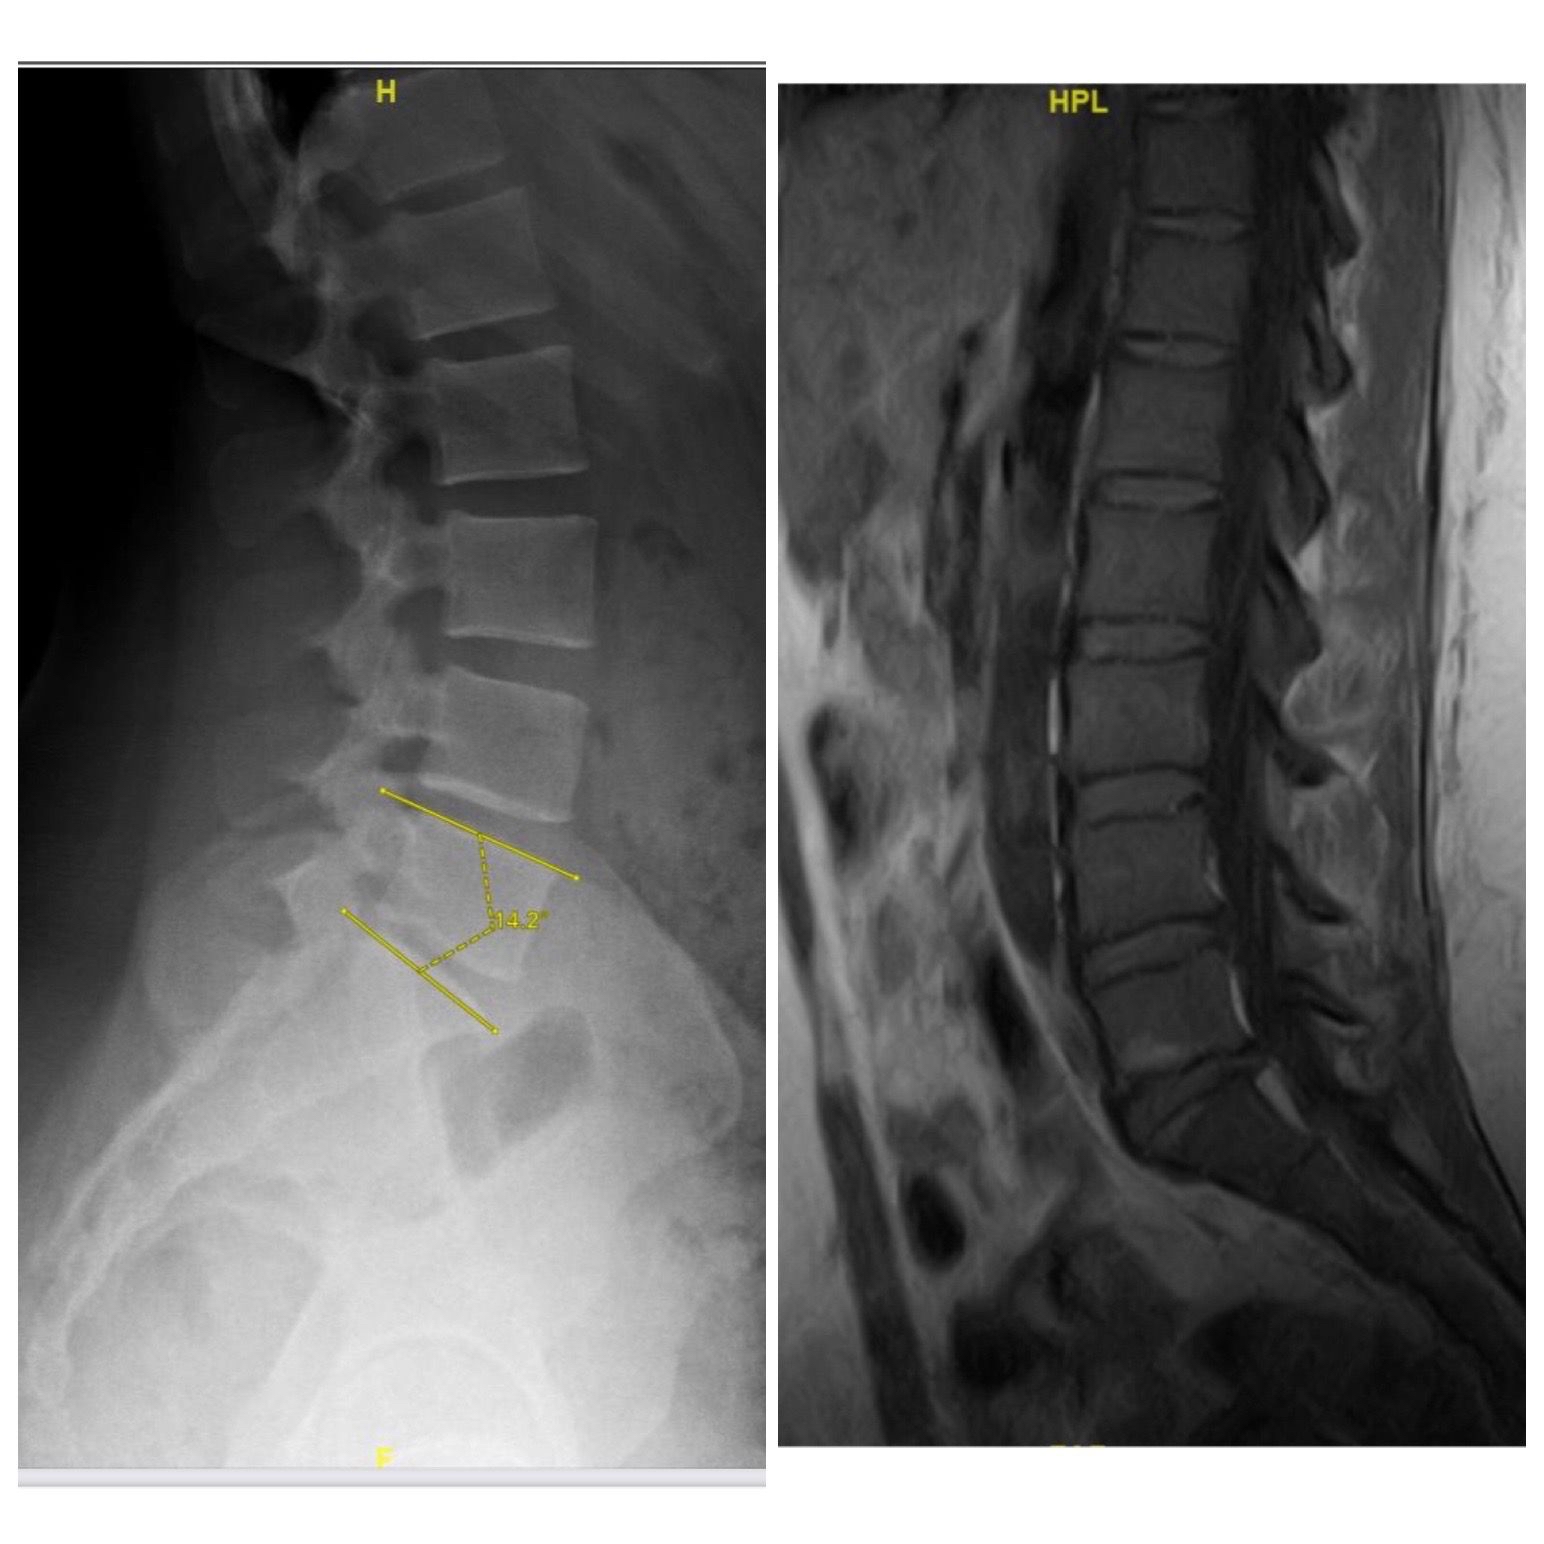

أجرى فريق طبي بقيادة أستاذ مساعد جراحة المخ والأعصاب والعمود الفقري بمستشفى الملك فهد الجامعي بالخبر التابع لجامعة الإمام عبدالرحمن بن فيصل، الدكتور سلطان السالمي، عملية تغيير لغضروف الفقرات القطنية عن طريق البطن لشابة تعاني من الآلام أسفل الظهر تبلغ من 28 عامًا.

وتابع أن هذه العملية تعد من العمليات المعقدة خاصة أن المريضة كانت تعاني من الآلام منذ خمس سنوات، وتمكنت من إجراء العملية وتماثل المريضة للشفاء وذلك بتقنية حديثة لمعالجة الآلام الظهر المزمنة وقد استغرقت مدة العملية ساعتين.